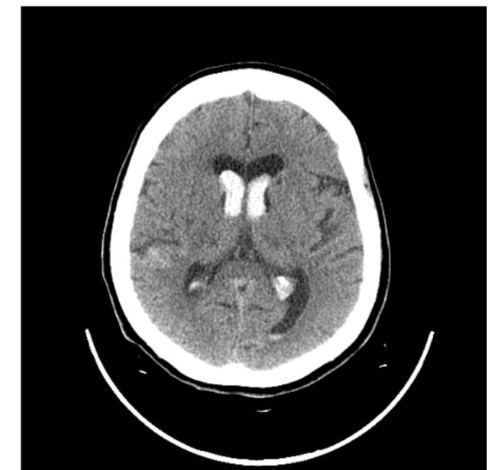

What is the pathology?

• Ischaemic stroke: blood flow to

the brain has been blocked.

• Hypodense areas = infarct (dead

brain tissue)